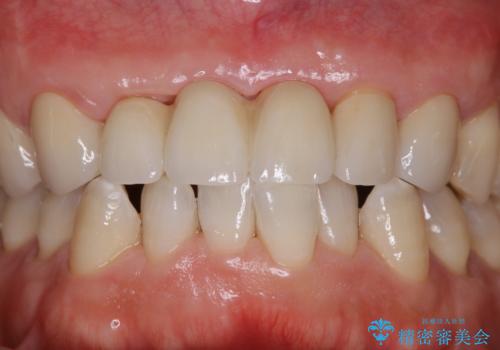

セラミックのチェックと合わせてPMTC